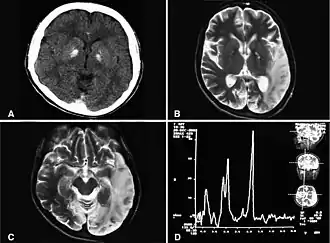

![]() Двусторонняя кальцификация базальных ганглиев, легкая атрофия мозжечка, ишемические изменения, повышение лактата. Abu-Amero et al., 2009[1] | |